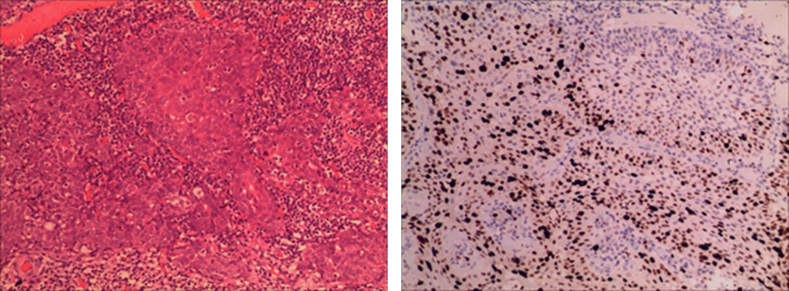

ESD标本术后病理:2-7块组织中分化鳞癌,M2,浸润模式:INFa,癌旁伴高级别上皮内瘤变(1-7块组织),镜下肿瘤范围约:1.8cm×1.2cm,肉眼分型:Type0-Ⅱb型,肿瘤未累及导管,血管(0),淋巴管(0),水平切缘(0),垂直切缘(0)。免疫组化结果示:CD31(血管侵犯-);D2-40(淋巴管侵犯-); Ki-67(80%+);P53(+)。

image.png

图3 右侧下咽部早期癌病理